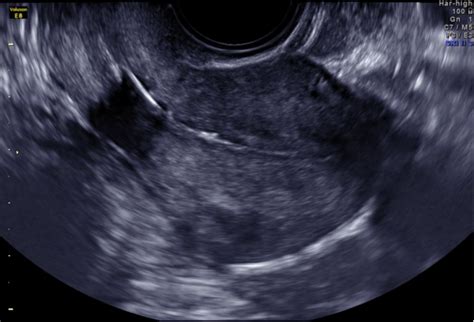

Ultrazvukové vyšetrenie orgánov malej panvy umožňuje získať podrobné informácie o stave ženských pohlavných orgánov. Toto vyšetrenie je bezbolestné a slúži na posúdenie tvaru a veľkosti maternice, štruktúry jej stien a stavu vnútornej sliznice maternice. Vyšetrením sa posudzuje veľkosť a tvar maternice, prítomnosť svalových uzlov (myómov), výška a kvalita sliznice maternice.

Toto základné vyšetrenie zisťuje priechodnosť či nepriechodnosť vajcovodov a zobrazuje tvar dutiny maternice. Jedná sa o ultrazvuk maternice a vaječníkov s ohľadom na fázu menštruačného cyklu a následné palpačné gynekologické vyšetrenie.